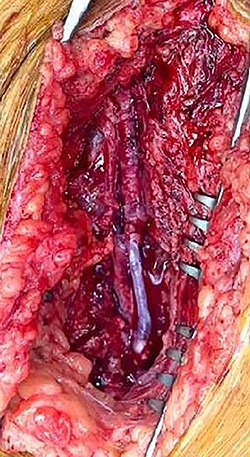

During operative intervention, a hematoma was observed involving muscle tissues in the anteromedial region of the thigh. There were no obvious signs of active infection. The proximal control obtained, the aneurysm incised and the distal control obtained. The aneurysm resected and samples collected for anatomopathological and microbiological analyses (Fig. 4). Reconstruction was performed by interposition of the ipsilateral great saphenous vein in reverse, with end-to-end anastomosis taking into consideration the diameter of the femoral artery (Fig. 5). Intraoperative tissue cultures were negative and the anatomopathological analysis showed a histopathological aspect corresponding to a PSA of the femoral artery, with the absence of the arterial wall and without specific character.